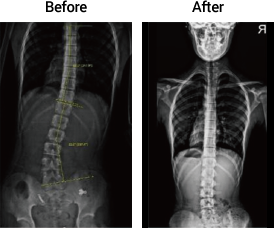

회전변형

18세 남성